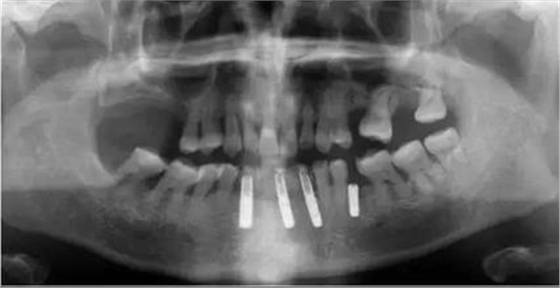

▲女性,42歲,牙周病,下前牙固定不良修復(fù)體,基牙炎癥、松動(dòng)。

▲拆除不良修復(fù)體,拔除松動(dòng)牙

▲下前牙數(shù)字化導(dǎo)板引導(dǎo)下種植后即刻修復(fù),6顆缺失牙,擬種植3-4顆

初診時(shí)下前牙不良修復(fù)體

拔牙前CT截圖

修復(fù)后全景片